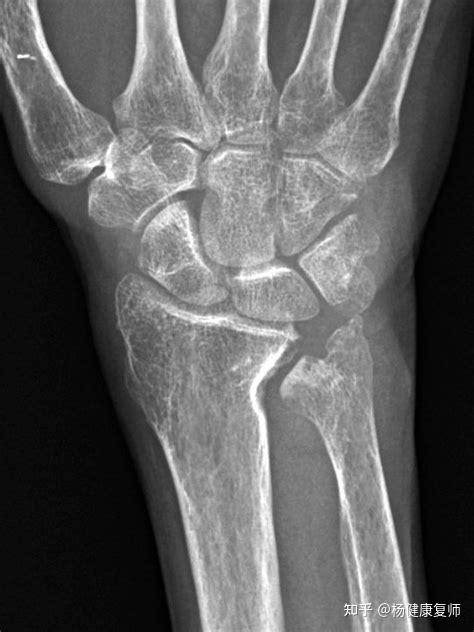

影像学检查以X线和MRI检查最具价值,通过X线检查可以判断尺骨变异类型并测量变异值发现月骨、三角骨骨质硬化和囊变,并排除骨折、腕关节炎等其他疾病。标准腕关节后前位X线检查时应保持行腕关节中立位,即肩关节外展90°肘关节屈曲90°,前臂呈中立位。若中立位未发现尺骨阳性变异,可在握拳、腕部旋前位时再次摄片,此时由于桡骨围绕尺骨旋转,导致其相对变短,部分患者可出现尺骨阳性变异。Jung等[8研究发现,前臂旋转时,尺骨变异可增加1.34mm。MRI检查可以发现月骨软骨软化及骨髓水肿等早期改变,也可以诊断TFCC损伤,具有较高的灵敏度和特异度。研究发现,UIS患者月骨软骨软化多发生在月骨掌侧,合并TFCC中央凹损伤的患者月骨软骨软化范围更大。